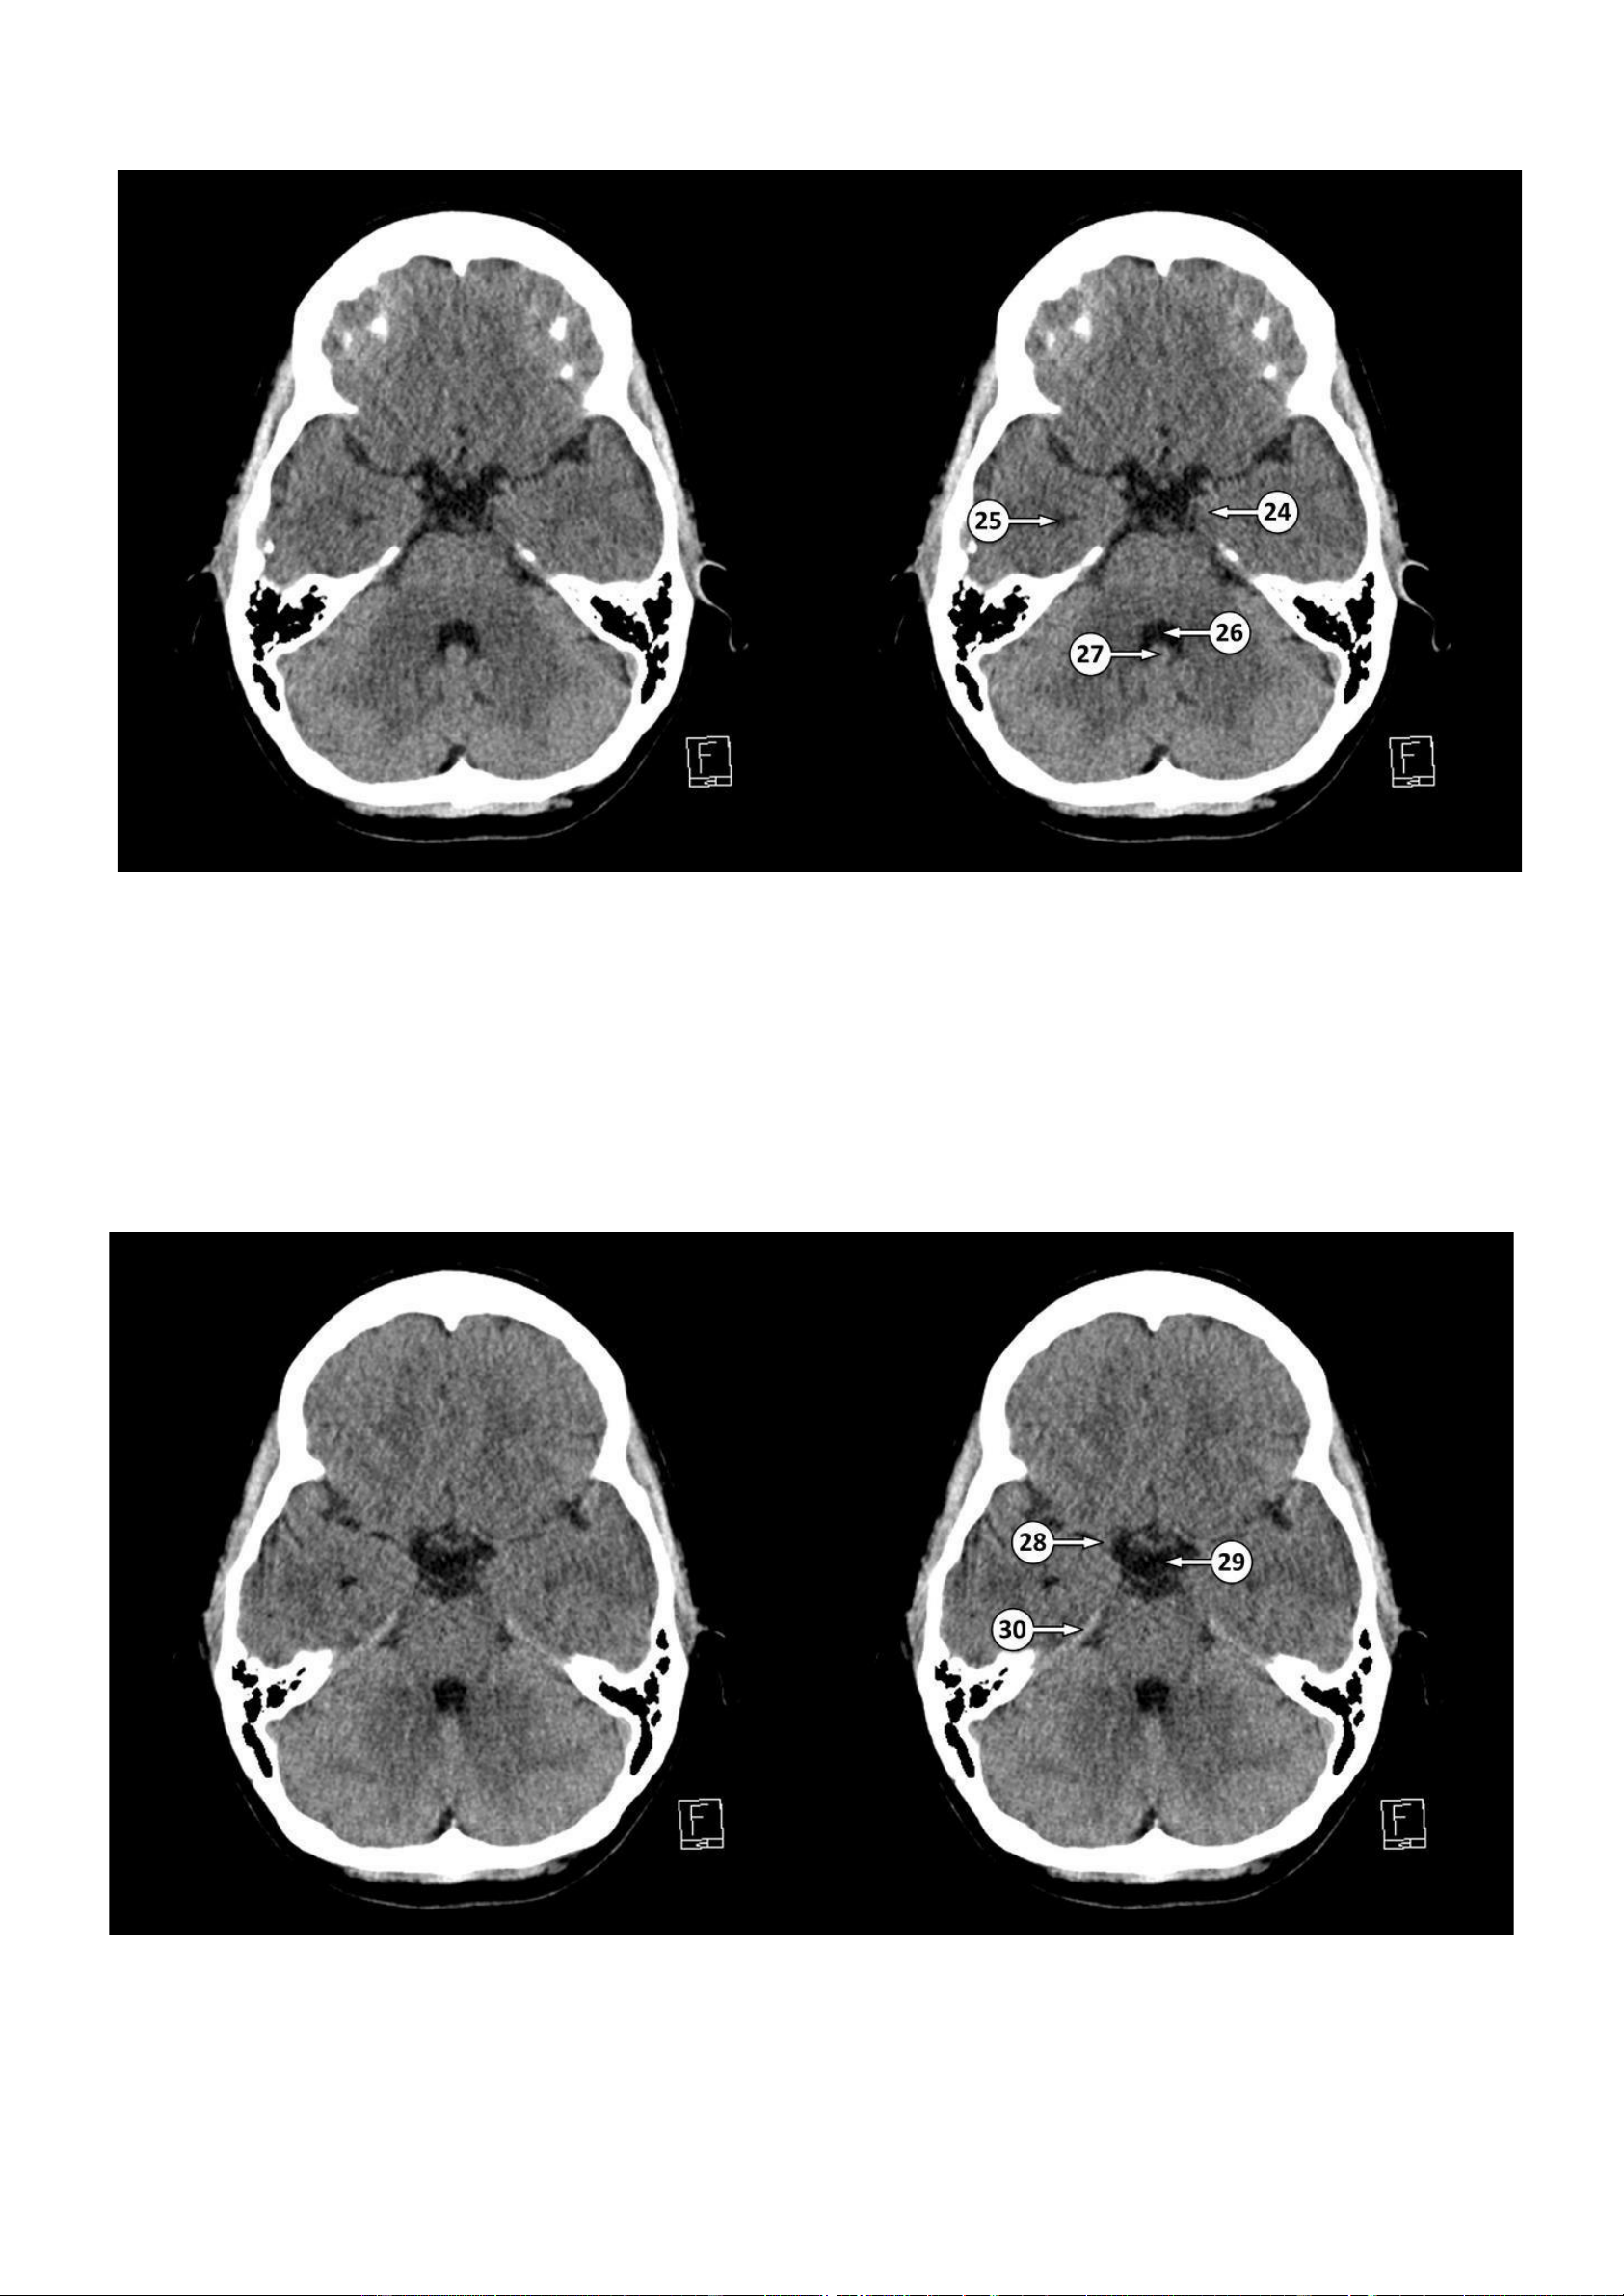

▪ Số 24: Móc hồi hải mã

▪ Số 25: Sừng thái dương của não thất bên ▪ Số 26: Não thất IV

▪ Số 27: Nốt của tiểu não

28: Đoạn M1 của động mạch não giữa 29: Bể trên yên 30: Lều tiểu não lOMoAR cPSD| 22014077